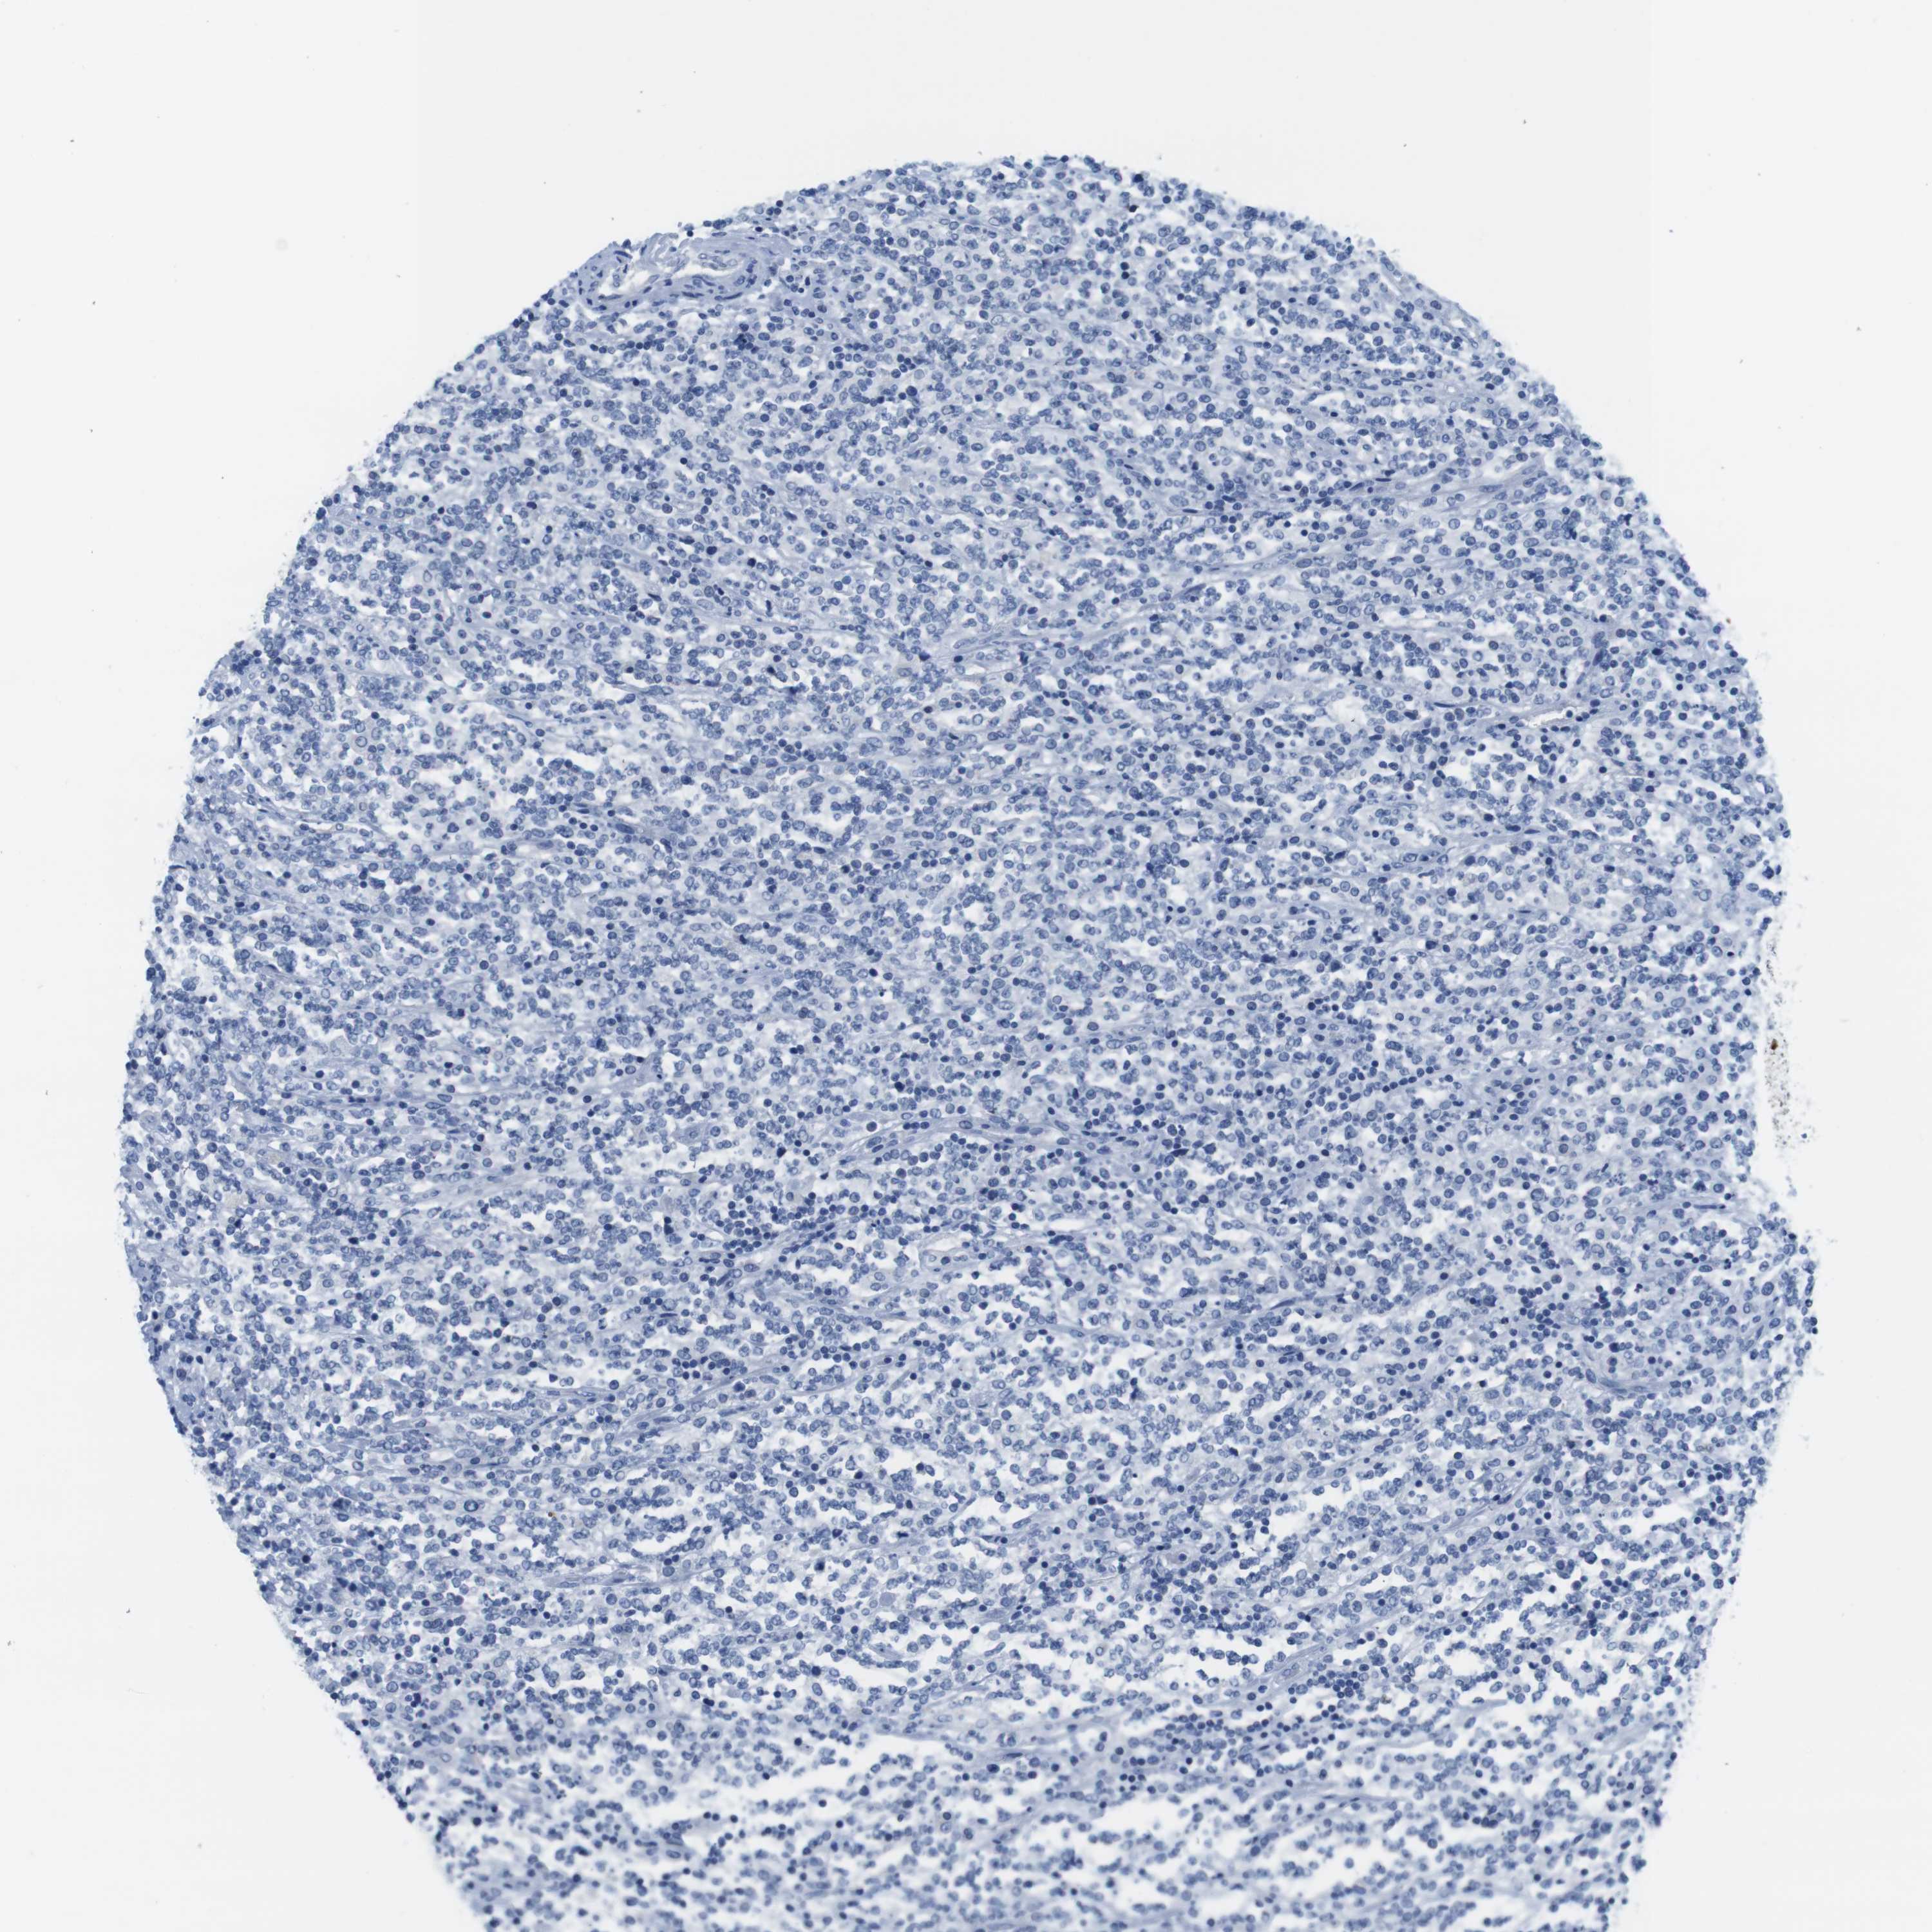

CANCER LYMPHOMA Show tissue menu

LYMPHOMA - Protein expressioni

A mouse-over function shows sample information and annotation data. Click on an image to view it in a full screen mode. Samples can be filtered based on level of antibody staining by selecting one or several of the following categories: high, medium, low and not detected. The assay and annotation is described here.

Each image is clickable and will lead to virtual microscopy that enables deeper exploration of all samples and also displays staining intensity scores, fraction scores and subcellular localization as well as patient and tissue information for each sample.

Antibody HPA039061

Antibody HPA039062

Antibody CAB015442

Antibody CAB022600

Hodgkin's disease, NOS

Malignant lymphoma, non-Hodgkin's type, High grade

Malignant lymphoma, non-Hodgkin's type, Low grade